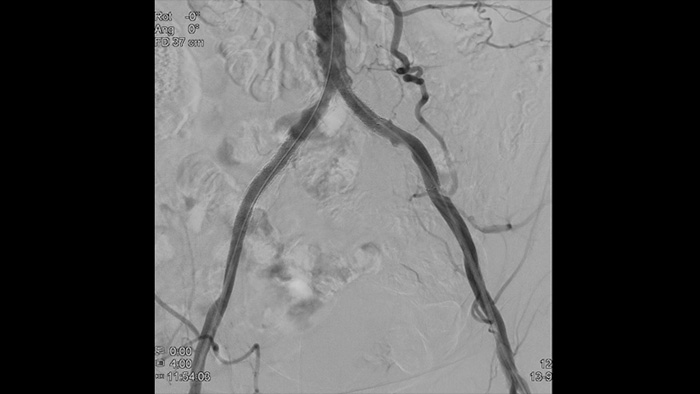

Hochauflösende Bilder von Gefäßen mit hervorragender Detailgenauigkeit zur Unterstützung durchdachter Behandlungsstrategien, präziser Navigation und Verlaufsbeobachtung